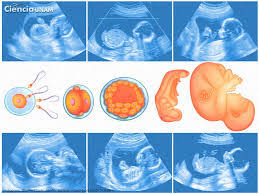

La pertinencia de este evento está en la necesidad de  incrementar los resultados cientÃficos de proyectos interdisciplinarios y multicéntricos en temáticas como la estimulación prenatal, estrés y embarazo, Teratogenicidad embriofetal inducida por medicamentos, Impacto de la infertilidad en el envejecimiento poblacional de la sociedad cubana, Genética molecular del desarrollo, su relación con la infertilidad e Impacto de la EmbriologÃa y la Reproducción Asistida en el Programa de Atención Materno Infantil (PAMI).

Durante los años de formación de los estudiantes de las ciencias médicas reciben los contenidos de EmbriologÃa en primer y segundo año pero se trata de un contenido aplicado  en el resto de los años de la carrera, ya sean en Ginecoobstetricia, PediatrÃa o CirugÃa y otras vinculadas a la parte clÃnica.